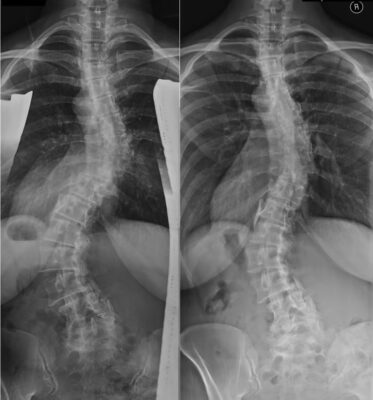

Wie man ein Röntgenbild einer leichten Skoliose interpretiert: Frühe Anzeichen einer Wirbelsäulendeformität erkennen

Learn how to interpret a minor scoliosis X-ray and spot early signs of spinal deformity. [...]